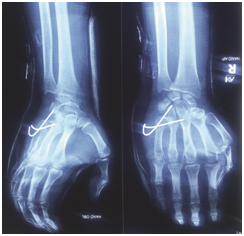

After 1 week the cock-up slab was removed during first follow up. Swelling of Right hand fully subside. Blood circulation intact. Nerve sensation and fingers movements are normal. Encourage finger movements. After 3 weeks both k-wires removed on second follow up. The stability of fifth carpometacarpal joint checked both clinically and radiologically. Also the Indian salutation test was negative. Slight tenderness at fifth carpometacarpal joint with moderate stretch. Encourage both active and passive movement of fingers and wrist joints. After 6 weeks during third follow up, slight tenderness on fifth carpometacarpal joint with deep stretch. All movements of wrist and hand were free. He started motor bike ride. After 3 months, on fourth follow up, the patient regain full functions of injured hand (Right). The grip strength was fully satisfactory (Figure 1–5).

Figure 3 Post operative follow up after one week (Removal of cast and allow movement of the hand) Radiographic view AP & Oblique.

Figure 4 Postoperative follow up after 3 weeks, removal of k-wire. Radiographic view AP & Oblique after k-wire removal.